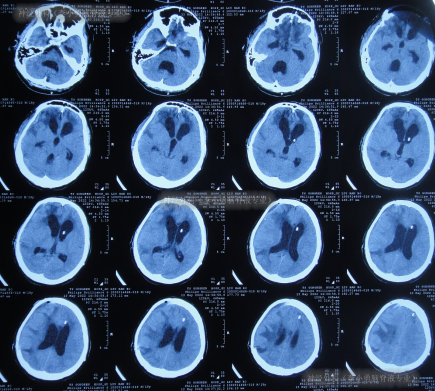

患者于2022年2月2日,不慎摔倒头部磕到地面,当时呈嗜睡状态,呕吐1次,大小便失禁,由120急送至当地县某医院,查头颅CT示右额部血肿(片子丢失),当即转至上级的河北省唐山市某医院,查头颅CT示右额部血肿、脑疝(图-1);检查期间出现昏迷、呕吐、四肢强直。

图-1:2022年2月2日头颅CT